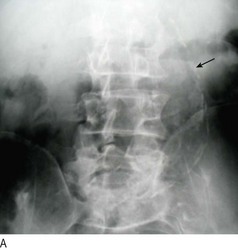

Fig. 6.37 Abdominal aortic aneurysm.

(A) Abdominal X-ray showing calcification (arrow). (B) Computed tomography of the abdomen showing an abdominal aortic aneurysm (arrow). (C) At laparotomy the aorta is seen to be grossly and irregularly dilated.

Clinical examination is unreliable in establishing the presence or size of an AAA; if in any doubt, obtain an ultrasound scan of the aorta. In the UK there is now an ultrasound-based AAA screening programme for men as they reach their 65th birthday.

A ruptured AAA can be difficult to diagnose because many patients do not have the classical features of abdominal and/or back pain, pulsatile abdominal mass and shock (hypotension). The most common misdiagnosis is renal colic (a man, >60 years, presenting with ‘renal colic’ has a ruptured AAA until proved otherwise). If there is any suspicion of a ruptured AAA speak to a vascular surgeon straight away who will probably request an immediate contrast-enhanced CT of the abdomen (if the patient is cardiovascularly stable).